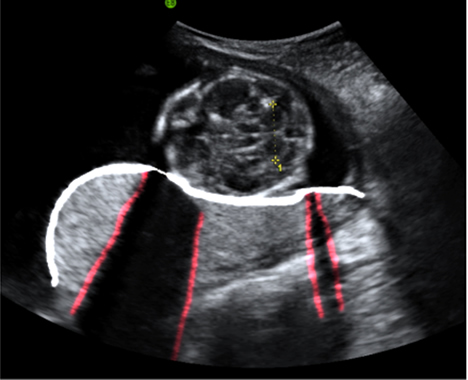

This image shows the posterior placenta - situated on the back wall of the uterus. Notice how the normal homogeneous nature is partly obscured by shadowing from overlying bony structures (in this case, the fetal skull).